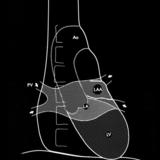

Right chambers lat

Date: 03/02/2006

Views: 2310